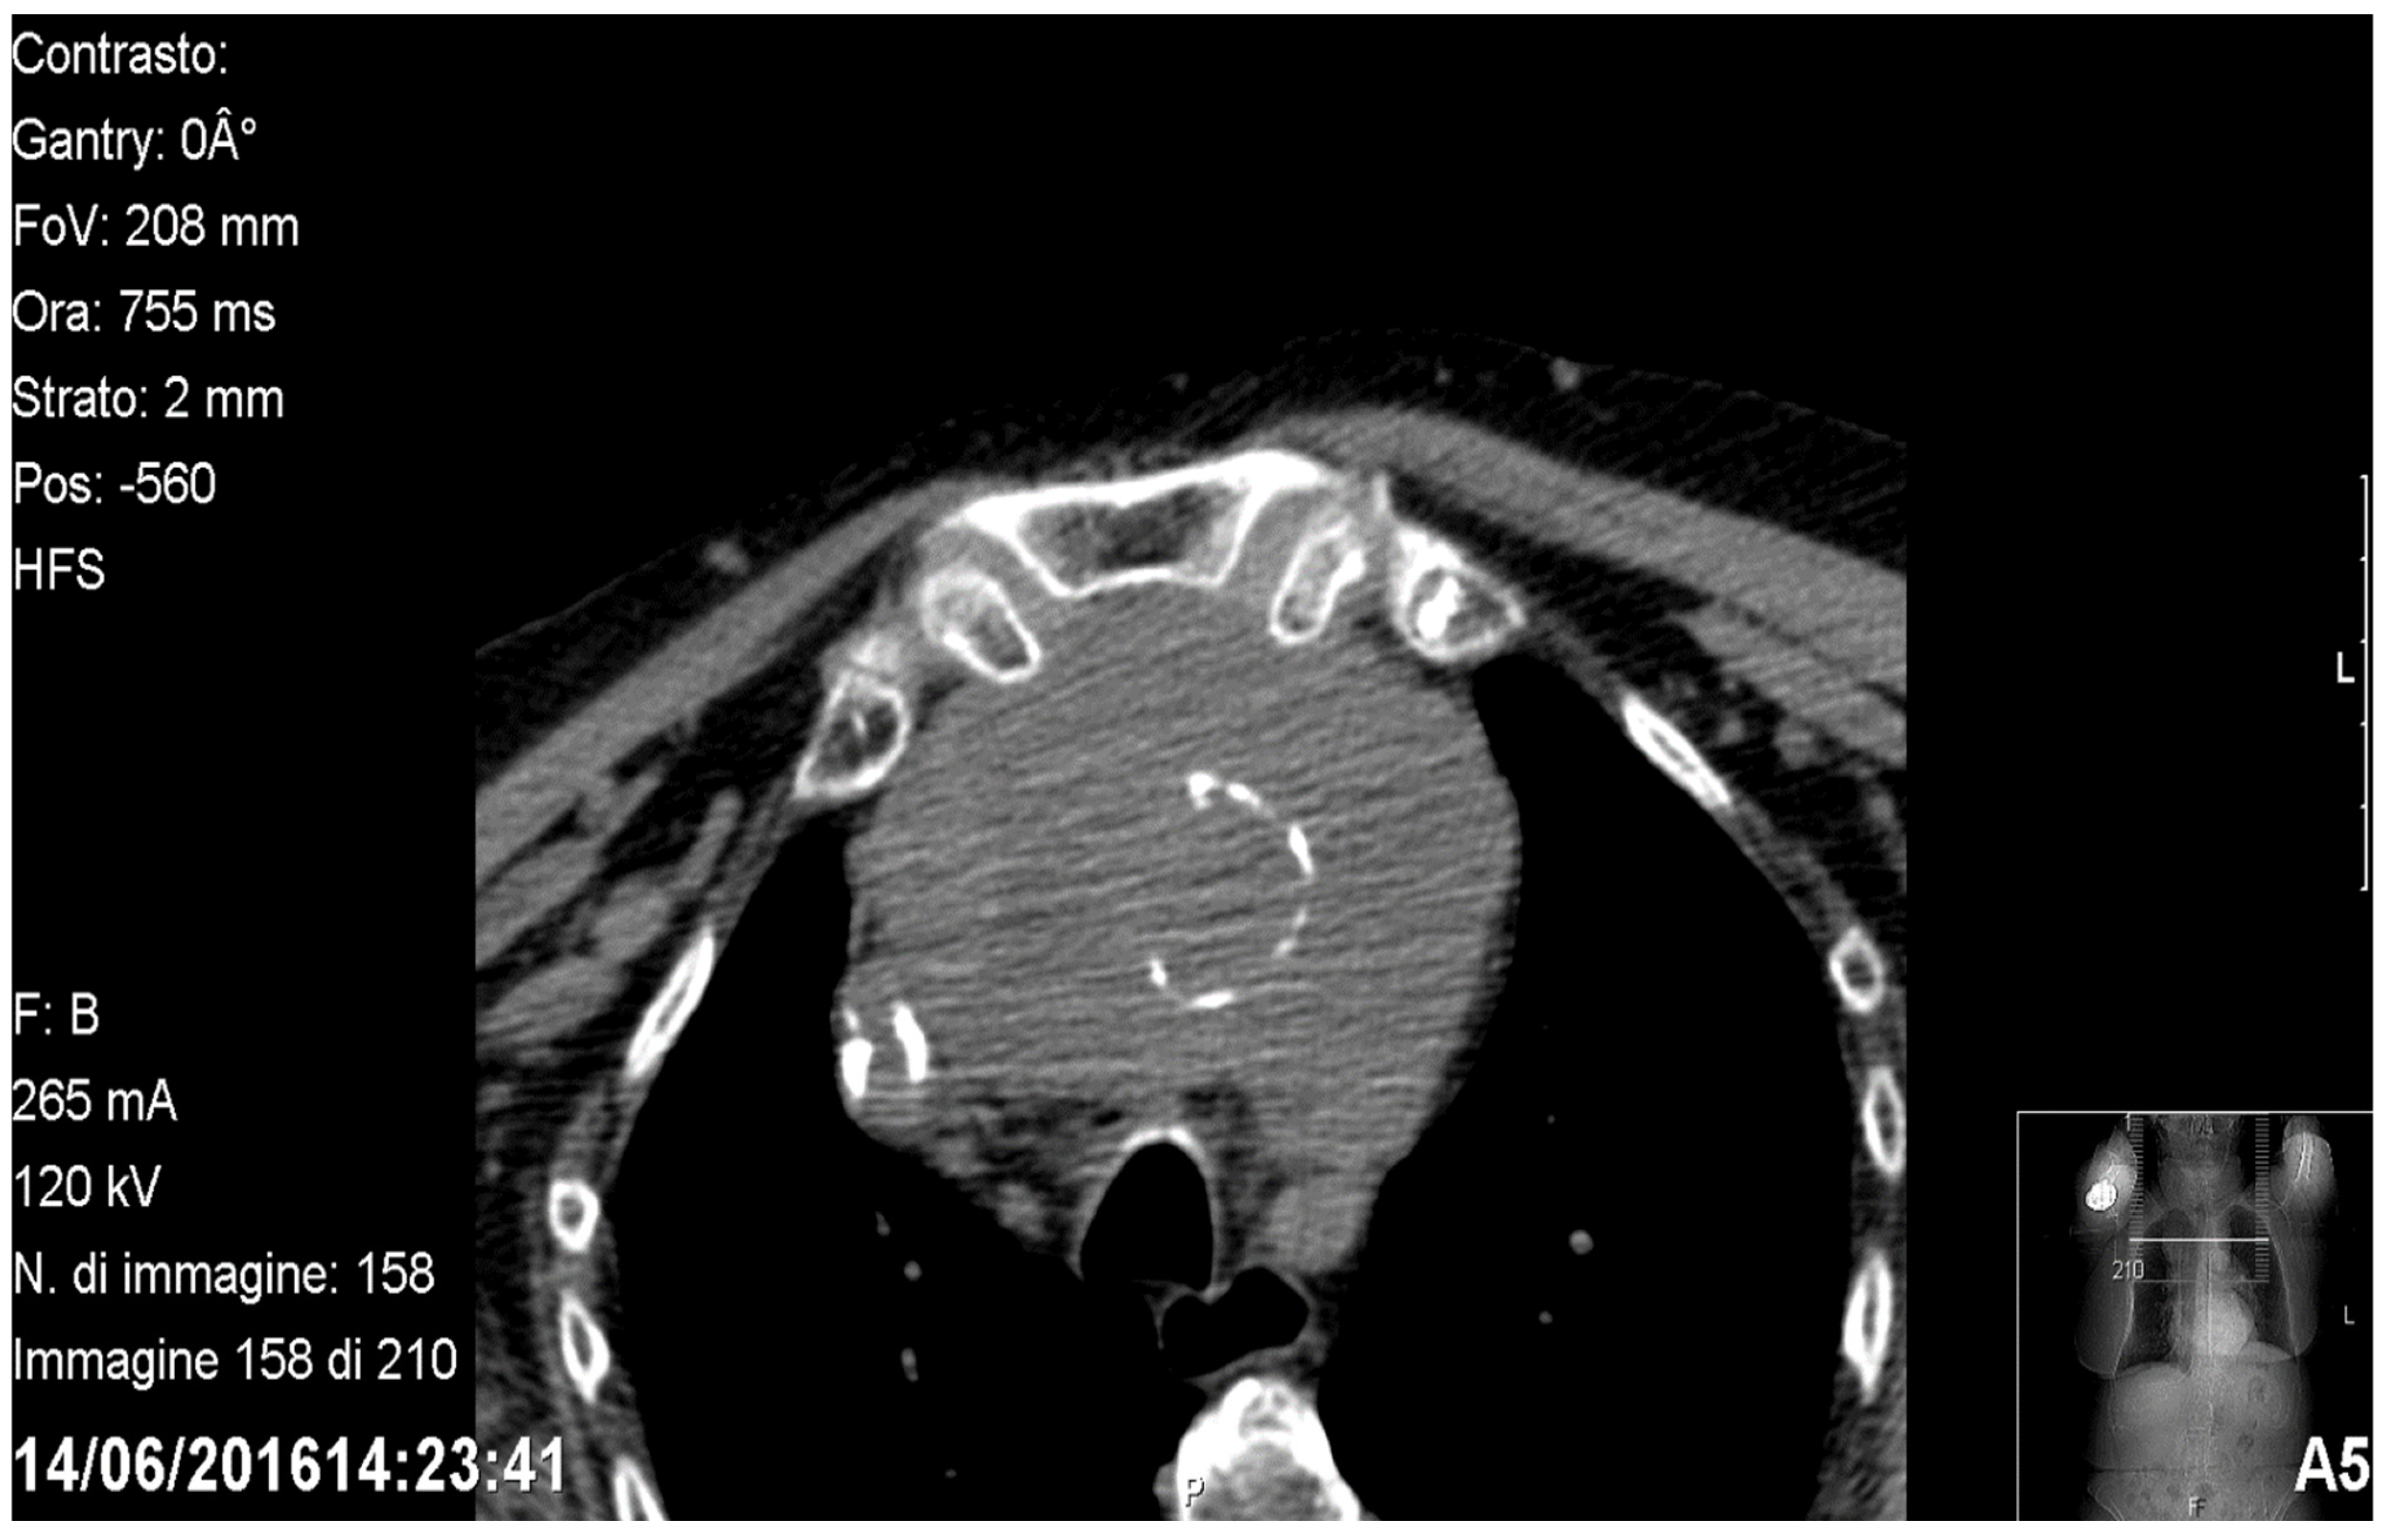

Figure 2.

Sagittal CT showing a retrovascular retrosternal goitre.